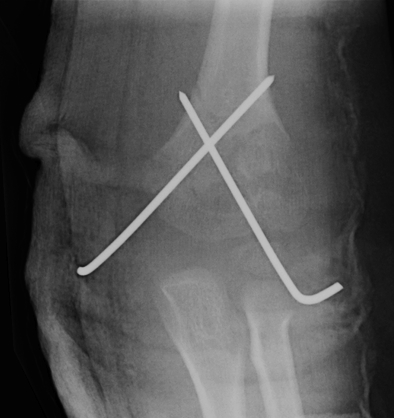

- lateral K wires

- crossed K wires

- systematic review and meta-analysis

- 11 studies (RCTs and prospective cohorts)

- 1158 patients

- loss of reduction in 11.6% of crossed K wires and 12.4% of lateral K wires

- iatrogenic ulna nerve injury in 4% crossed K wires and 0.3% lateral K wires

Carrazzone et al. J Should Elbow Surg 2021

- meta-analysis of 12 RCTs

- no difference in functional outcome

- reduced risk of iatrogenic nerve injury with lateral K wires

- greater fixation stability and less loss of reduction with crossed K wires

2 x lateral K wires

Advantage

- no risk to ulna nerve

Disadvantage

- if not correctly done, can be unstable

2. Crossed K wires 1.6mm

- increased biomechanical strength

- maybe necessary with signification medial comminution

- maybe necessary if unstable after two lateral K wires

- ulnar nerve at risk